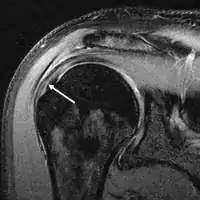

MRI

Magnetic resonance imaging (MRI) and ultrasound[46] are comparable in efficacy and helpful in diagnosis, although both have a false positive rate of 15–20%.[47] MRI can reliably detect most full-thickness tears, although very small pinpoint tears may be missed. In such situations, an MRI combined with an injection of contrast material, an MR-arthrogram, may help to confirm the diagnosis. It should be realized that a normal MRI cannot fully rule out a small tear (a false negative) while partial-thickness tears are not as reliably detected.[48] While MRI is sensitive in identifying tendon degeneration (tendinopathy), it may not reliably distinguish between a degenerative tendon and a partially torn tendon. Again, magnetic resonance arthrography can improve the differentiation.[48] An overall sensitivity of 91% (9% false negative rate) has been reported, indicating that magnetic resonance arthrography is reliable in the detection of partial-thickness rotator cuff tears.[48] However, its routine use is not advised, since it involves entering the joint with a needle, with the potential risk of infection. Consequently, the test is reserved for cases in which the diagnosis remains unclear.

Diagnostic modalities, dependent on circumstances, include X-ray, MRI, MR arthrography, double-contrast arthrography, and ultrasound. Although MR arthrography is currently considered the gold standard, ultrasound may be most cost-effective.[34] Usually, a tear will be undetected by X-ray, although bone spurs, which can impinge upon the rotator cuff tendons, may be visible.[35] Such spurs suggest chronic severe rotator cuff disease. Double-contrast arthrography involves injecting contrast dye into the shoulder joint to detect leakage out of the injured rotator cuff,[36] and its value is influenced by the experience of the operator. The most common diagnostic tool is magnetic resonance imaging (MRI), which can sometimes indicate the size of the tear, as well as its location within the tendon. Furthermore, MRI enables the detection or exclusion of complete rotator cuff tears with reasonable accuracy and is also suitable for diagnosing other pathologies of the shoulder joint.[37]

Clinical judgement, rather than over-reliance on MRI or any other modality, is strongly advised in determining the cause of shoulder pain, or planning its treatment, since rotator cuff tears are also found in some without pain or symptoms. The role of X-ray, MRI, and ultrasound is adjunctive to clinical assessment and serves to confirm a diagnosis provisionally made by a thorough history and physical examination. Over-reliance on imaging may lead to overtreatment or distract from the true dysfunction causing symptoms.[39]